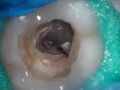

Odbudowa zębów po leczeniu kanałowym (...)

Katarzyna Olczak